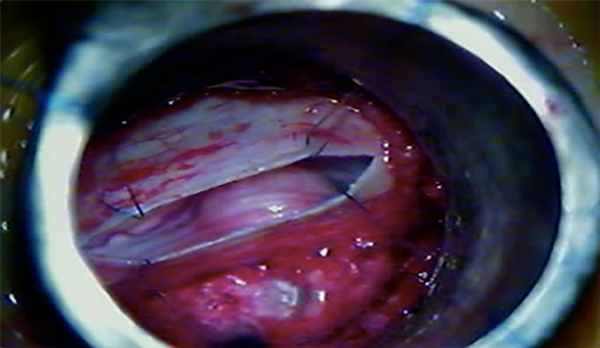

Cuando ya se encuentran en tracción los 4 puntos de reparo dural, los extremos de la incisión se aproximan entre sí, y eso permite incidir con bisturí dichos extremos para realizar una nueva tracción de los puntos de reparo, y así, una mayor exposición lateral (Fig. 7, 8 y 9).

Fig. 7: Ojal dural mediante retracción dural transtubular

Fig. 8: Disección tumoral separando la duramadre por apertura insuficiente.